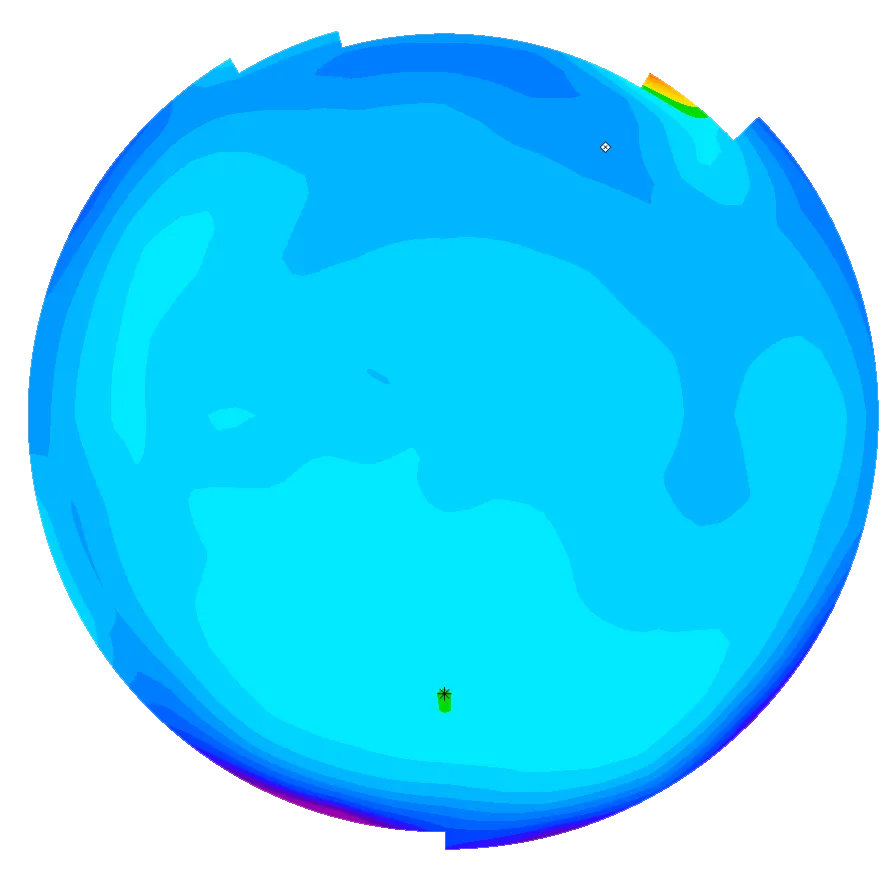

Eine normale gesunde Hornhaut ist glatt und zeigt eine gleichmässige Dicke. Die Form der Hornhaut ähnelt einem Ball, mit einer identischen Rundung in alle Richtungen.

Dank neuester Technologien sind wir heute in der Lage, sowohl die vordere als auch die hintere Oberfläche der Hornhaut mit extrem hoher Präzision zu messen. Dank dieser verbesserten Genauigkeit können Anomalien bereits in sehr frühen Stadien erkannt werden, was zu schnelleren und zuverlässigeren Diagnosen führt. Erkrankungen wie Keratokonus oder Pellucid Marginal Degeneration (PMD) lassen sich nun deutlich früher als bisher diagnostizieren, was die Patientenergebnisse verbessert und eine rechtzeitige Behandlung ermöglicht.

Die moderne OCT-Technologie für den vorderen Augenabschnitt bietet eine ultrahochauflösende Darstellung des Hornhautgewebes und ermöglicht eine unglaublich detaillierte Visualisierung seiner Struktur. Dieses Mass an Präzision ist ein grosser Vorteil bei der Nachsorge von Hornhauterkrankungen und der postoperativen Überwachung. Sie ermöglicht es den Ärzten, subtile Veränderungen der Hornhaut im Laufe der Zeit mit grosser Genauigkeit zu verfolgen.